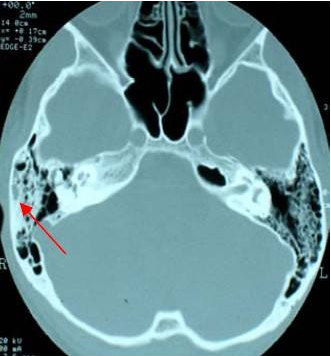

2、慢性乳突炎的症状表现:慢性乳突炎主要分为三种。前列类是单纯型中耳乳突炎会导致乳突气房发育障碍,乳突呈硬化型。较为严重的就会导致乳突骨质破坏,第二类即骨疡型中耳乳突炎会导致鼓窦及乳突骨质坏死,形成肉芽组织,通过乳突片可见鼓窦扩大,乳突骨质破坏。第三类胆脂瘤型中耳乳突炎,其胆脂瘤经上鼓室、鼓窦会扩展到乳突,通过X射线片可以看见典型边缘清楚的空洞。

在中耳乳突炎早期治疗时,可采用抗生素等药物治疗来控制病情。如果耳内脓液排脓不畅就需要进行鼓膜切开术进行引流。如果病变深达骨质或出现可疑并发症就应该立即进行手术治疗。我院配备的内窥镜、电测听、CT等检查设备可对患者耳部进行详细检查,根据病情症状确诊病因进行针对性治疗。